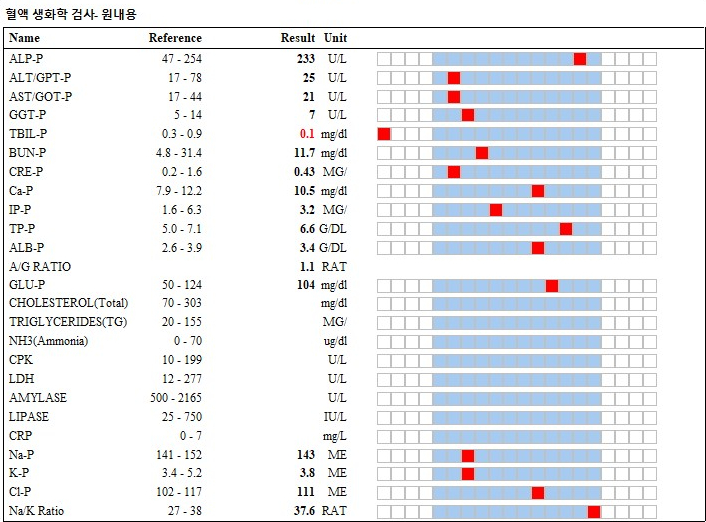

혈액검사에서 특이 소견은 관찰되지 않았습니다.